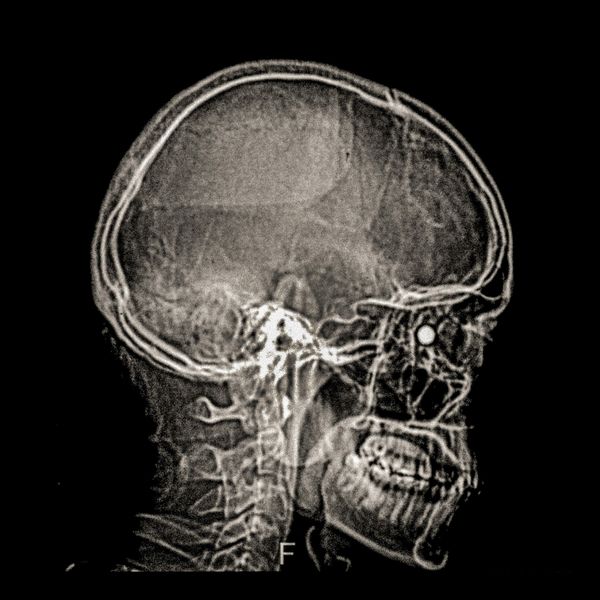

460 people have been seriously injured in their eyes, 34 of whom suffered total loss due to the indiscriminate use of pellets and tear gas bombs by the Carabineros de Chile special forces. The Carabin

460 people have been seriously injured in their eyes, 34 of whom suffered total loss due to the indiscriminate use of pellets and tear gas bombs by the Carabineros de Chile special forces. The Carabineros fired their rubber bullets and tear gas guns directly into the faces of the protesters during the Chilean social outbreak between late 2019 and early 2020. This figure has made Chile the country with the world record for eye mutilation by state and security forces.

By early March 2020, around 3,838 people had been injured and according to the Chilean Society of Ophthalmologists and human rights organizations, 460 of them ended up with serious eye complications, loss of the eyeball, and also loss of sight. This figure has made Chile a world record for eye mutilation, due to the indiscriminate use of pellets and tear gas bombs by special forces of the Carabineros, who have shot their weapons directly into the faces of the protesters.